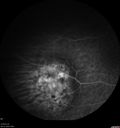

88 year old female with melanosis oculi and 2.5 mm elevated choroidal melanoma. She also has AMD with geographic atrophy. The right eye is the better eye. The left eye had a macular hemorrhage from wet AMD and breakthrough vitreous hemorrhage.